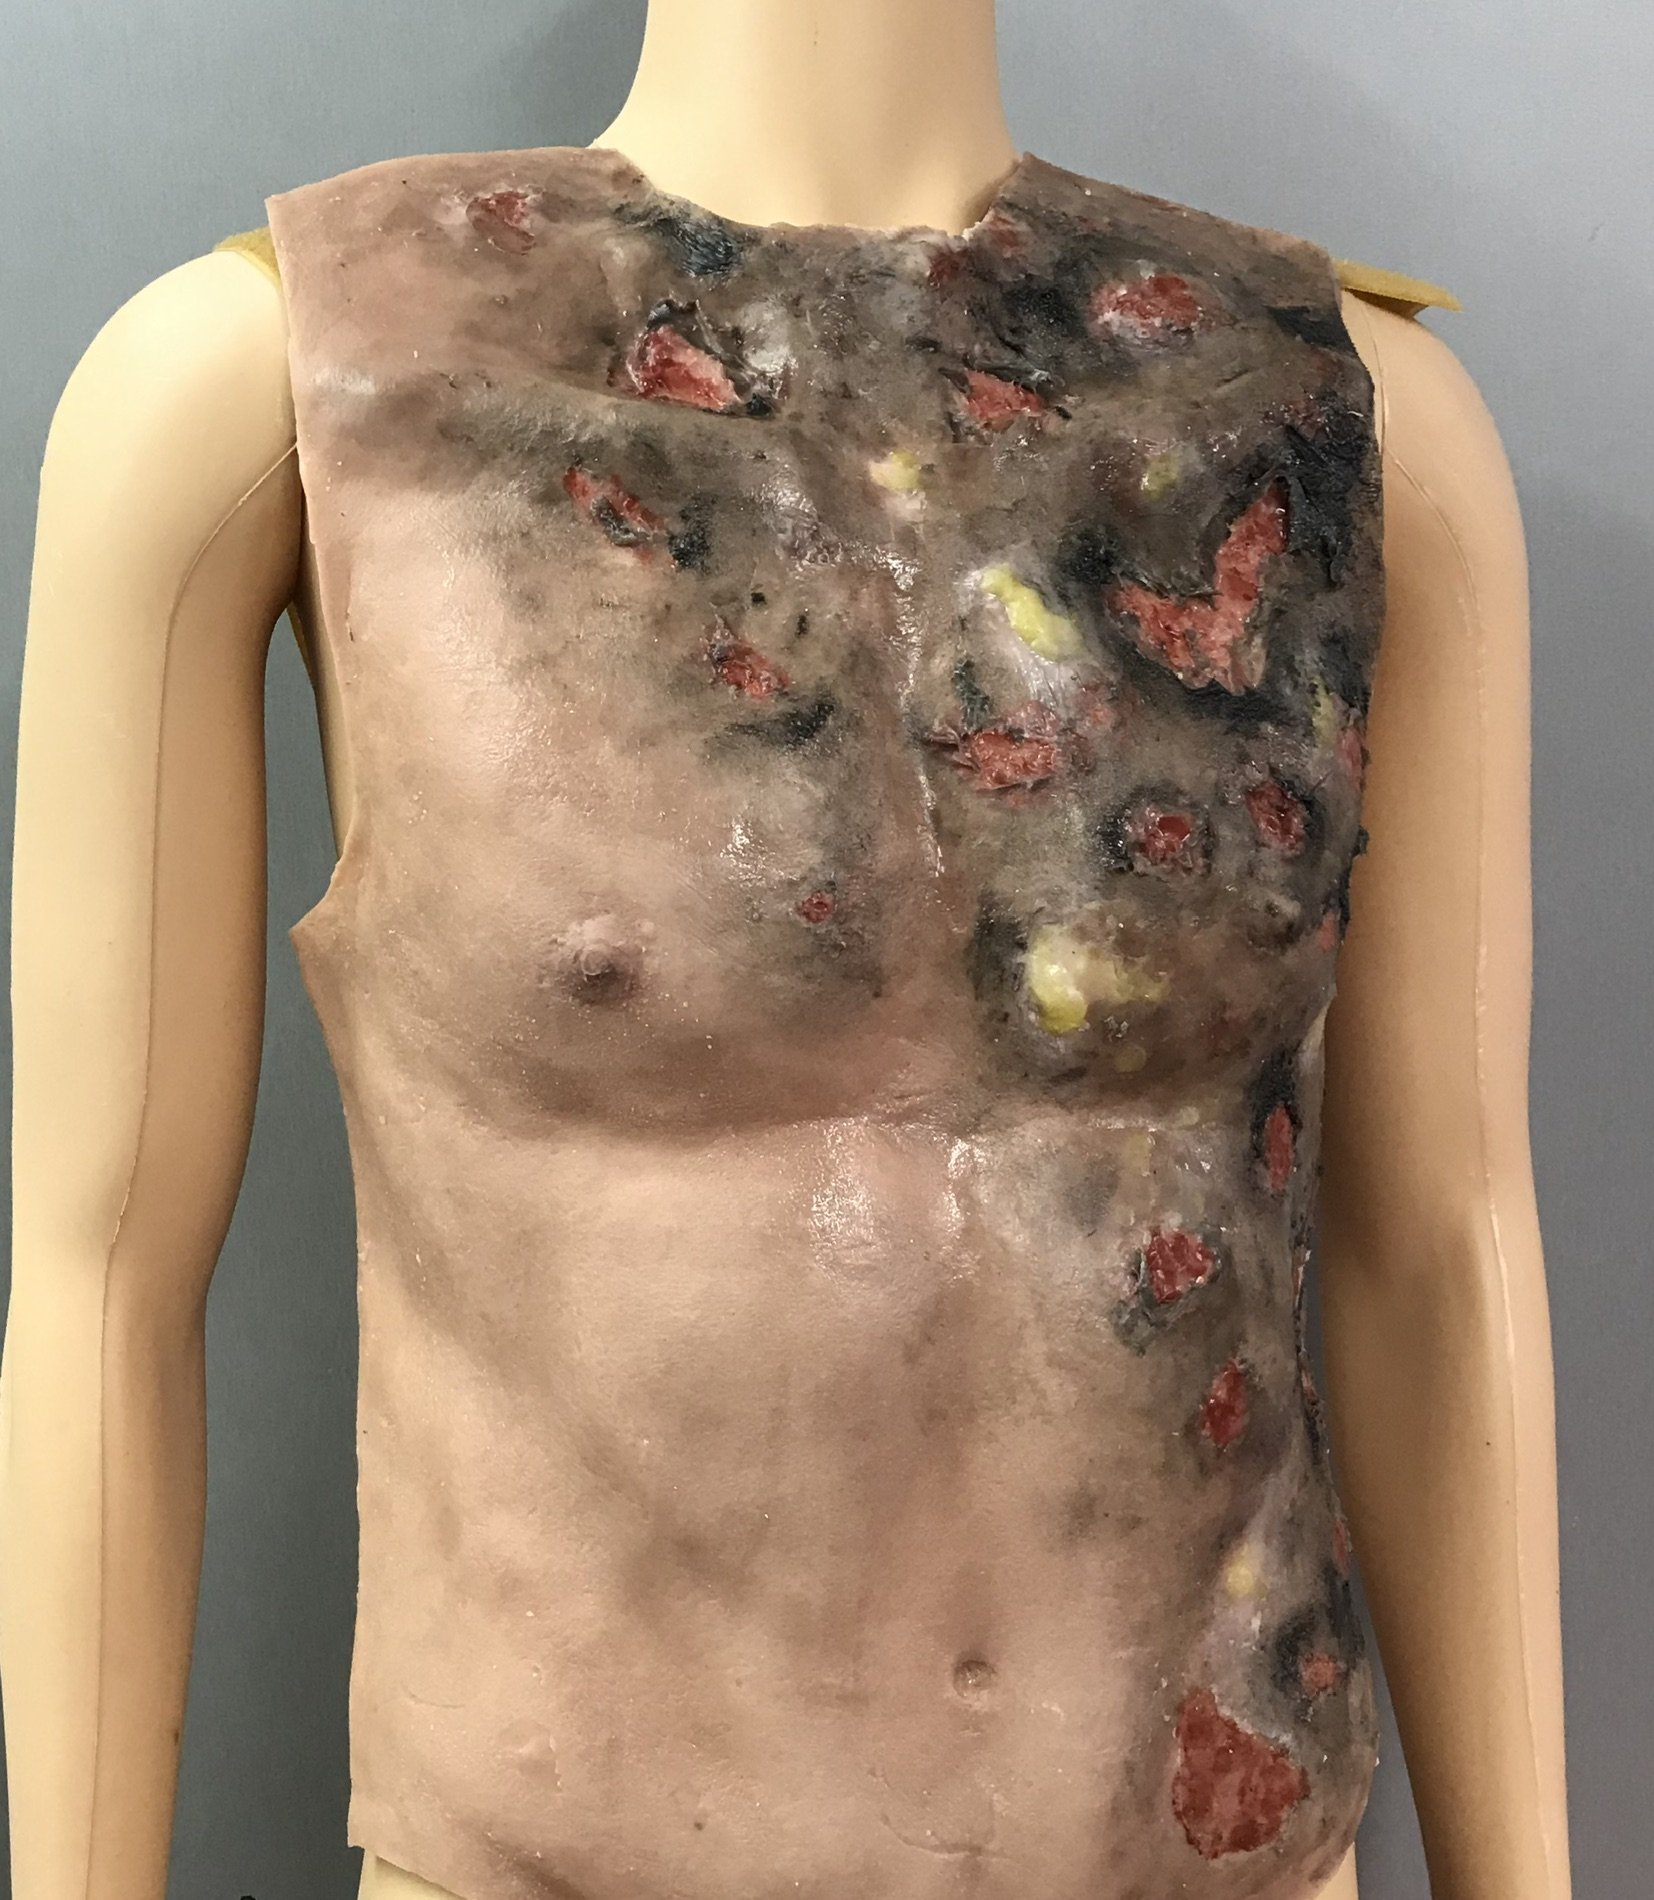

Poparzony tors MS310

Opis

Model torsu został zaprojektowany do celów symulacji urazów. Wykonany jest z wysokiej jakości silikonu z siateczkowym podkładem dla zwiększenia wytrzymałości.

Kategoria: Oparzenia